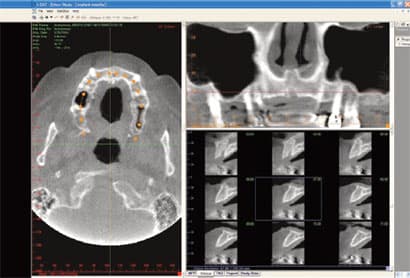

Here and Now and Beneficial For All

IN THE PAST, DENTAL DAYDREAMERS PONDERED THE ABILITY TO CAPTURE A 3-D IMAGE OF THE MOUTH AND TO VIEW IT FROM ALL ANGLES. The ability to rotate that 3-D mode and zoom in on details was an even greater aspiration. Then, to coordinate all of the information for integration with other applications- such as guided implant placement software-promised to add even more value to the technology. All of these benefits are not just relegated to the dental visionaries of the future. 3-D imaging is available, here and now, and is actively improving practices across all dental disciplines. IMPLANTOLOGY Jack T. Krauser, DMD: 3-D radiography has made an astonishing and

Cone Beam CT: A Breakthrough Imaging Technology for Dentistry

ABSTRACT: Accurate images of the craniofacial region are critical for the development of a diagnosis and treatment plan. The Cone Beam CT (CBCT) Scanner represents a significant advance in imaging capabilities for all disciplines of dentistry. This new-generation scanner uses computed tomography technology to provide a complete three-dimensional view of the maxilla, mandible, teeth, and supporting structures with relatively high resolution and low radiation exposure to the patient. This article discusses some of the technical aspects of CBCT and its possible dental usages. INTRODUCTION: Images of the craniofacial region comprise an important component of the dental patient record. Ideally, the imaging process begins with the development of an imaging goal. The imaging

Exploring Cone Beam 3–D Dental Imaging

2-D imaging (standard film and digital X-rays) has long been the standard for dental scans-despite the somewhat costly price and high radiation dosages. Now 3-D imaging technology is set to address these issues. Cone Beam technology obtains crucial information at much higher resolution using lower radiation, and is cost-effective for practitioners and patients. Indeed, such important benefits will certainly give traditional 2-D X-ray imaging a run for its money. THE INTRODUCTION OF CONE BEAM TECHNOLOGY Here's where 3-D imaging is invaluable. It lets dentists see patients' anatomies in all dimensions by creating a 360° analysis. These images give dental professionals a complete makeup of the human jaw, face, and